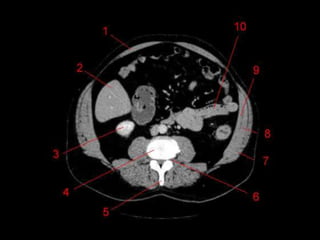

Subdivisão Funcional • Osoito segmentos são divididos: – A primeira divisão é realizada dividindo através da Porta Hepática, em esquerdo (I a IV) e direito (V a VIII) – A divisão é feita baseada em um relógio – Caudado é o segmento I – No ‘lobo’ esquerdo, o IV separa-se do II e do III pela veia hepática esquerda, representado anatomicamente pelo ligamento falciforme. – II e III se dividem através de uma linha imaginária transversal na altura da porta hepática. – No ‘lobo’ direito, se divide os segmentos através de uma linha transversal e pela veia hepática direita.

Subdivisão Funcional • Fundamentalimportância para Ressecção. • Maioria das lesões são do fígado direito.